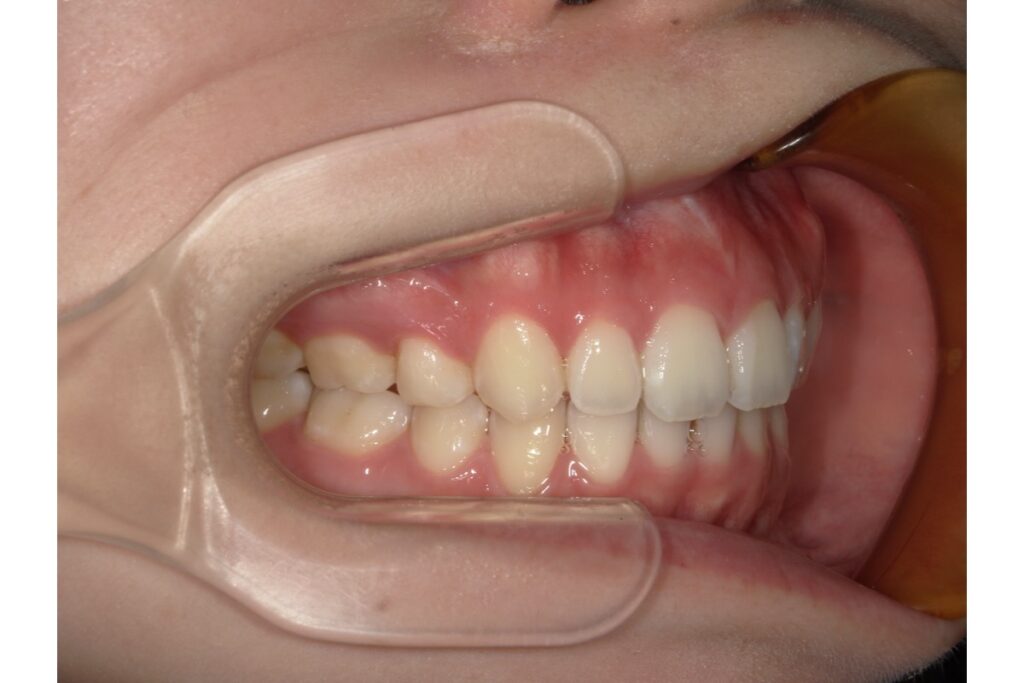

治療終了時の歯並び写真がこちらです↑

治療期間は、約1年半。その期間中に2回マウスピース作り直しをしています!

歯を抜いて治療を行っているので、横から見たときの変化がとても分かりやすいかと思います。歯だけではなく、横顔も口元がスッキリしますよ。